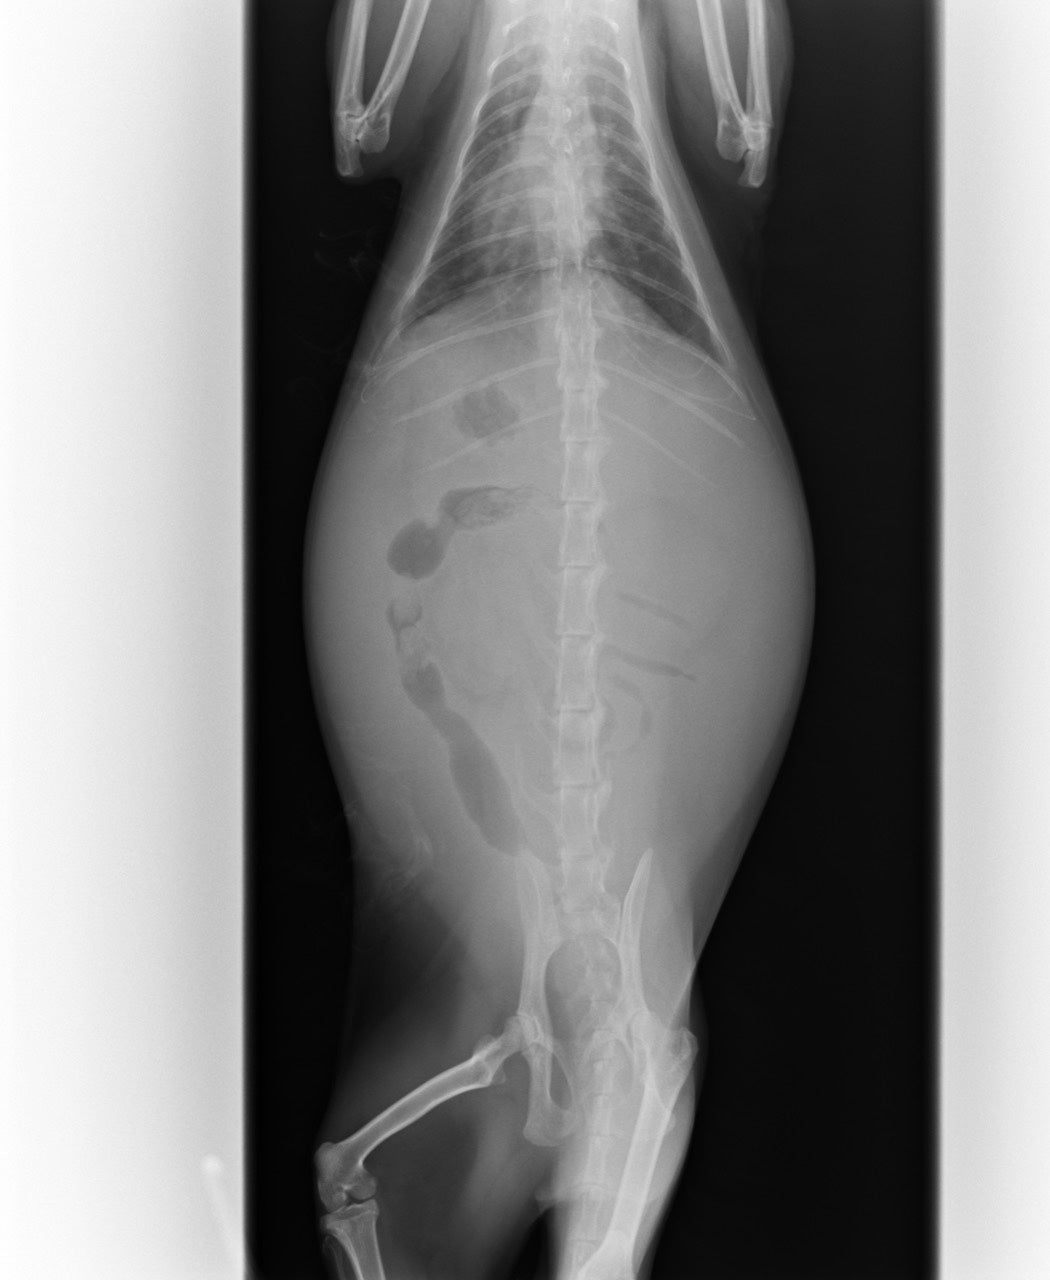

沢山の腹水がたまっており、PCR検査をしました。

腹水の量と色、超音波、血液検査の結果でFIP暫定診断となりました。

腹水だけではなく肉芽腫もあることがわかり、

ウェットタイプとドライタイプの混合で、中期FIPと診断されました。

ピエロは現在3.6kgなので、まずは1日1回550mgの投薬をはじめています。